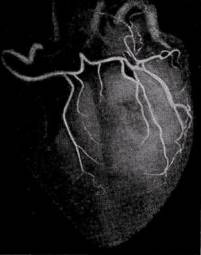

Коронарография является признанным "золотым стандартом" для выявления или исключения коронарной болезни сердца. Она позволяет определить выраженность сужения коронарных артерий, его локализацию и количество значительно стенозированных коронарных артерий (критерием такого сужения считается уменьшение площади просвета более чем на 70%)

Широкое применение селективной коронарографии и оперативных вмешательств на коронарных артериях сердца в последние годы позволило изучить анатомические особенности коронарного кровообращения живого человека, разработать функциональную анатомию артерий сердца применительно к реваскуляризирующим операциям у больных с ишемической болезнью сердца.